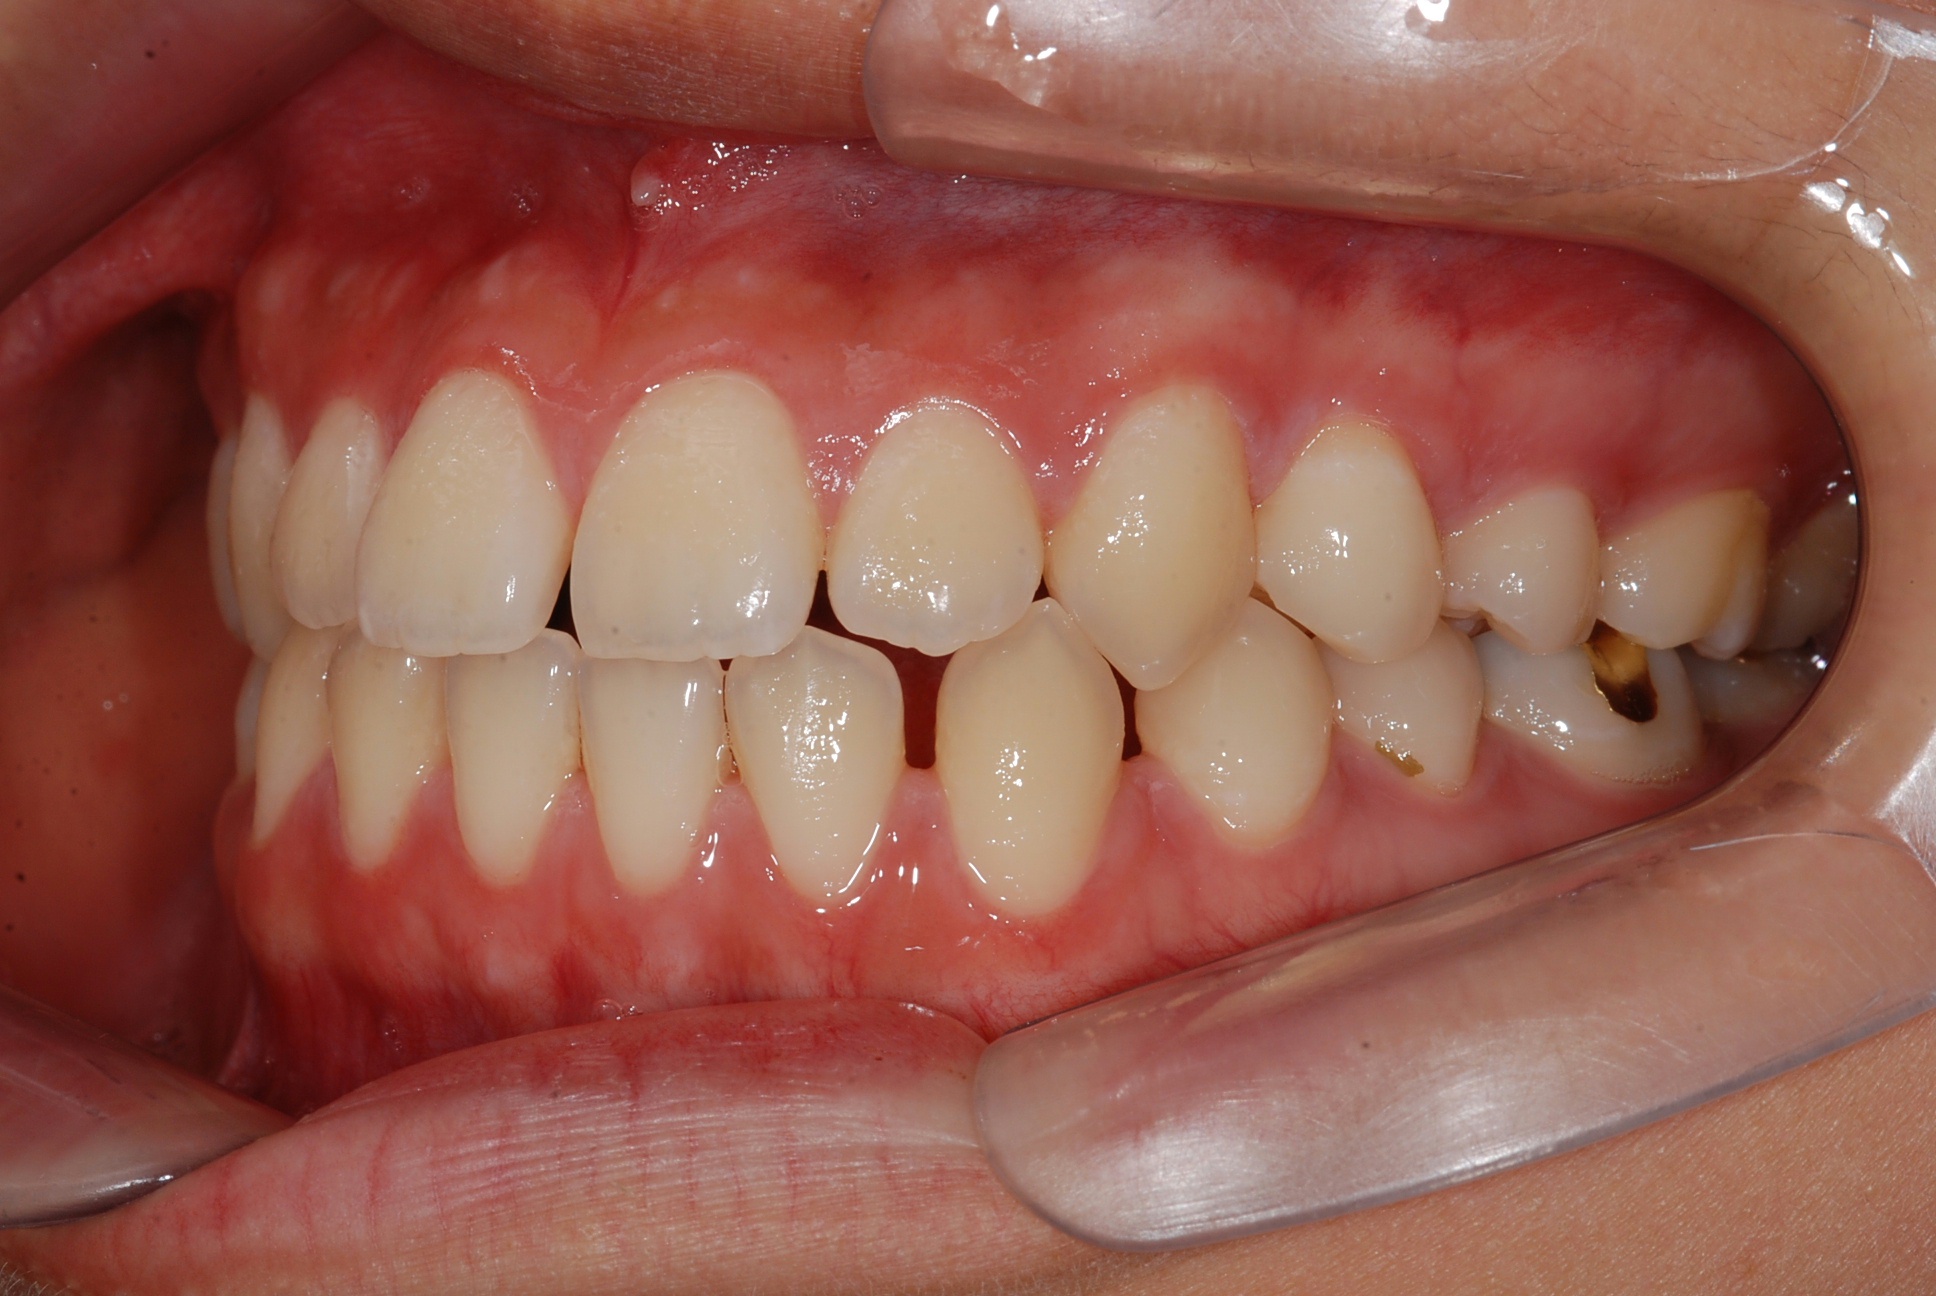

치료 후 사진입니다.